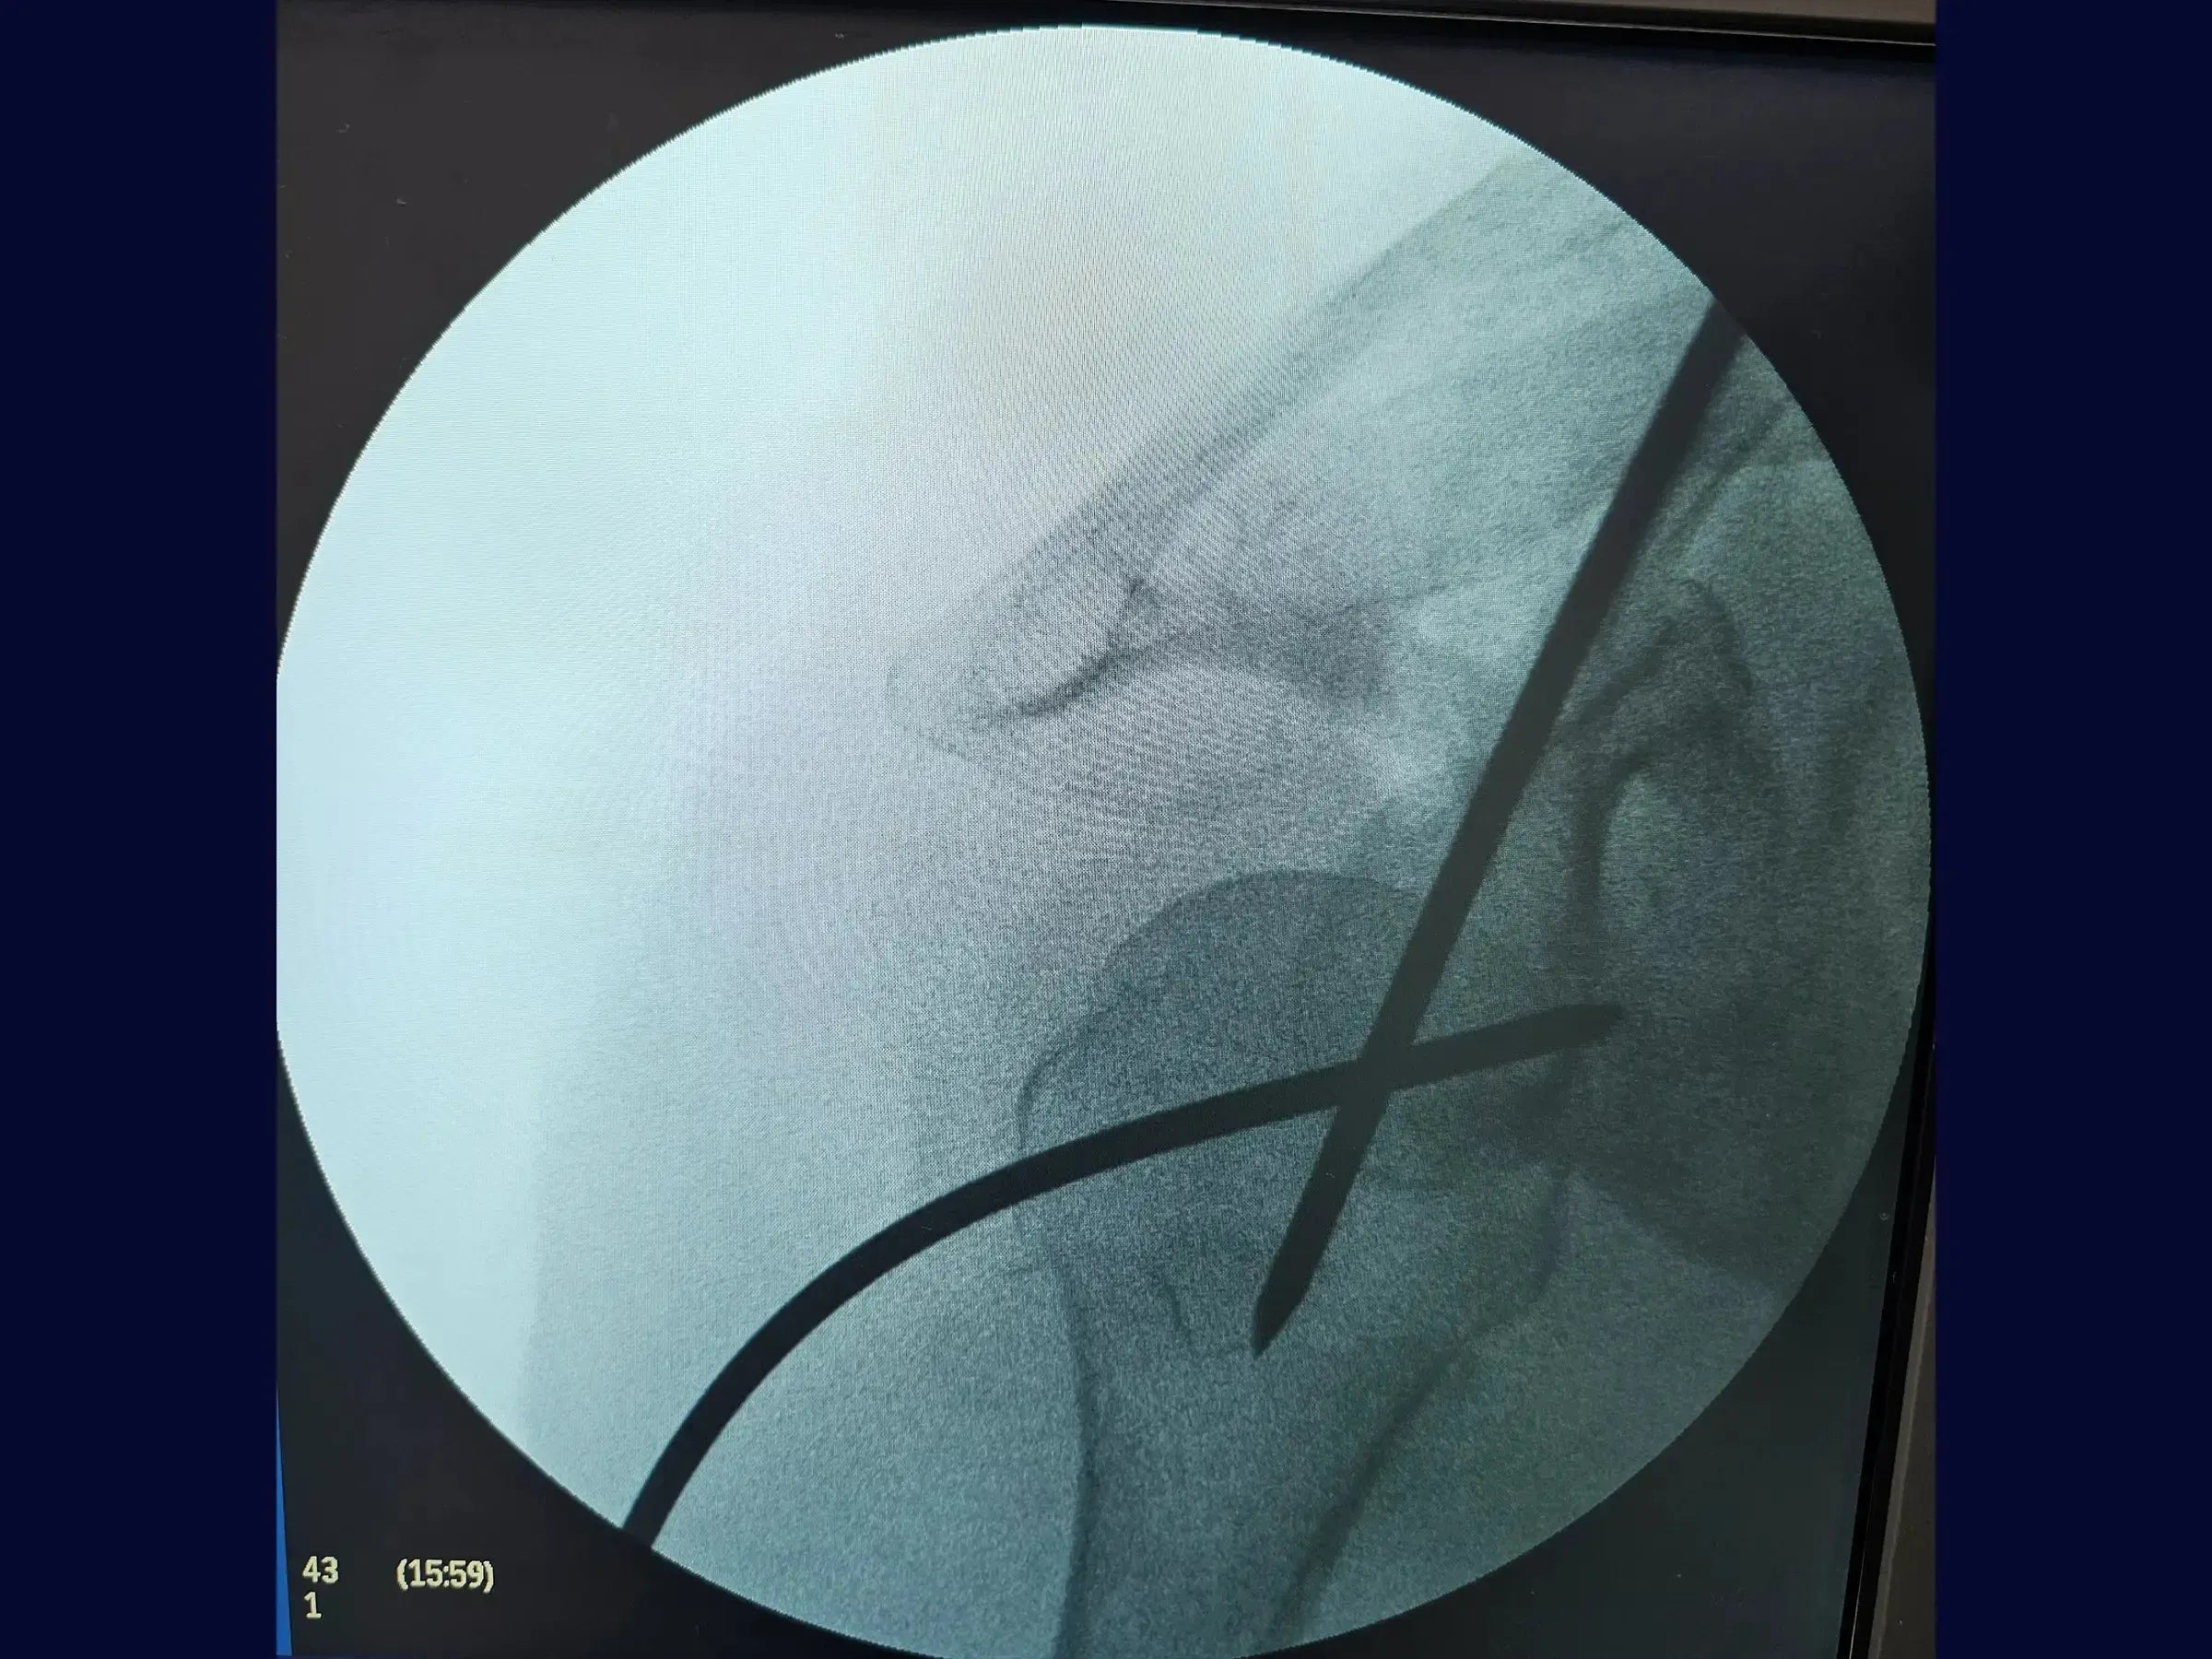

- Fixação com parafusos de bloqueio proximal e distal.

- Fixação Estável com Parafusos de Bloqueio: Metodologia para inserção de parafusos de bloqueio proximais e distais através de mini acessos, incluindo a fixação do calcar, com foco na recuperação do eixo, rotação e versão da cabeça umeral.

- Estratégias de Redução Funcional: Princípios de osteossíntese que priorizam a recuperação funcional e biomecânica do úmero, entendendo que a redução anatômica precisa não é essencial nesse tipo de fratura.